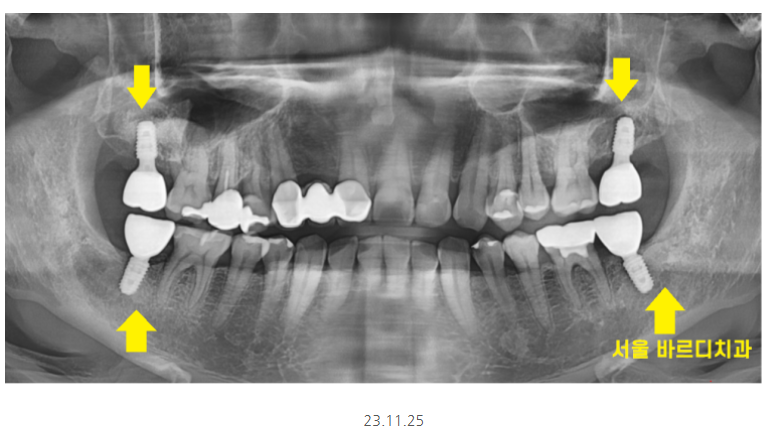

명일동 치과를 처음 방문하셨을 때 사진입니다.

보시는 것처럼

위, 아래

오른쪽, 왼쪽

사이좋게 양쪽 맨 끝 어금니를

상실하신 채 내원하셨어요.